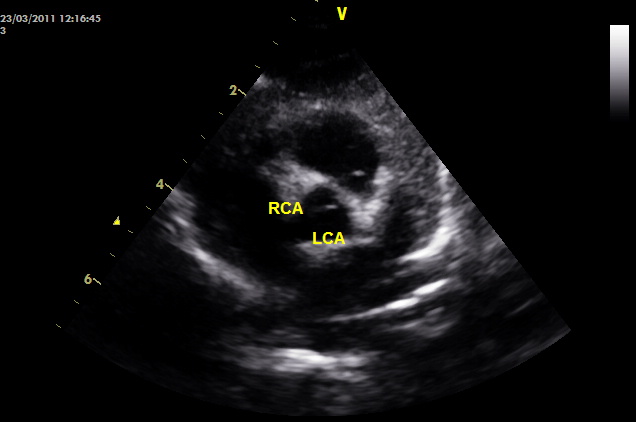

Υπερηχογράφημα (ECHO): φυσιολογική βασική ανατομία, φυσιολογικές διαστάσεις και λειτουργικότητα (συστολική και διαστολική λειτουργία, ελέγχθησαν και με ιστικό Doppler πέραν του συνήθους ελέγχου). Παρακάτω απεικονίζονται τα στεφανιαία. Ελέγχθηκε η έκφυση όχι μόνο με 2D, αλλά και με απεικόνιση της στεφανιαίας ροής με color Doppler (ασυνήθης πρακτική για παιδιά, θα εξηγηθεί ο λόγος στη συνέχεια).